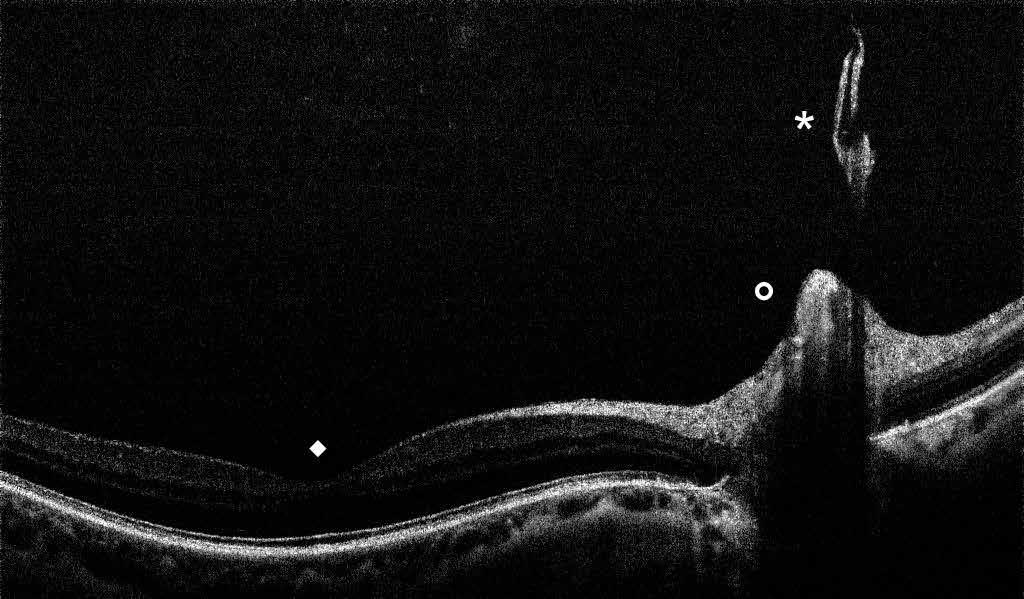

Figure 4. Multimodal imaging of a female diabetic patient affected by PDR that has already undergone complete laser photocoagulation treatment. 4A) UWF pseudocolor retinography showing complete laser photocoagulation treatment until vascular arcades; 4B-C) 12x12 and 4E-F) en-face WF-SS-OCTA of diabetic patient (4B, 4E) presenting FAZ enlargement, diffuse capillary drop-out and inferior mid-peripheral retinal nonperfusion areas, as compared to healthy patient (4C, 4F; 4D) Late phase UWF FA displaying diffuse BRB breakdwon, with perivascular leakage and non-perfusion areas.